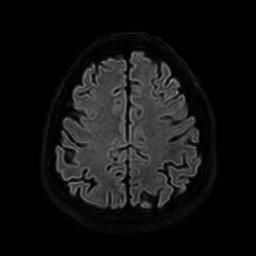

뇌 후두피질위축 봐주시면 감사하겠습니다(mri)

요즘 눈이랑 정신이 좀 이상해서 뇌mri를 찍었는데 이렇게 나오네요.

• 3번 째 사진

정확한 것은 정식 판독을 받아보아야 알 수 있겠습니다만, 개인적인 경험을 토대로 보았을 때에는 위축이 심하다고 보기에는 무리가 있어 보입니다. 뇌실이 비정상적으로 커져 보이지도 않고 뇌의 태두리가 두개골에서 많이 떨어져 있지도 않은 것이, 해당 사진들만 보아서는 위축이 심하고 치매를 의심하여야 한다 어떻다 판단을 내리기는 어려울 것으로 사료됩니다.